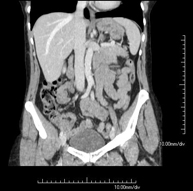

Prova diagnòstica que consisteix en l'estudi de l'abdomen d'alta definició anatòmica (fetge, vesícula biliar, via biliar, pàncrees, melsa, estómac, intestins, ronyons, estructures vasculars, bufeta, úter i ovaris, etc.) mitjançant l'ús d'un equip de TC (Tomografia Computeritzada). Aquestes imatges s'estudien posteriorment en una estació de treball que permet obtenir reconstruccions bidimensionals en diferents plànols de l'espai i també reconstruccions 3D (volumètriques). La majoria d'estudis requereixen l'ús de contrast iodat per millorar la definició de les imatges. - TC Pelvis

Prova diagnòstica que consisteix en obtenir imatges bi i tridimensionals de l'abdomen d'alta definició anatòmica (estructures òssies, estructures vasculars, fetge, pàncrees, vesícula biliar, ronyons, glàndules suprarenals, melsa, intestí prim i gros, bufeta, úter i ovaris, pròstata i vesícules seminals, urèters, etc.) mitjançant l'ús d'un equip de TC (Tomografia Computeritzada). La majoria d'estudis requereixen l'ús de contrast iodat. - TC Fetge